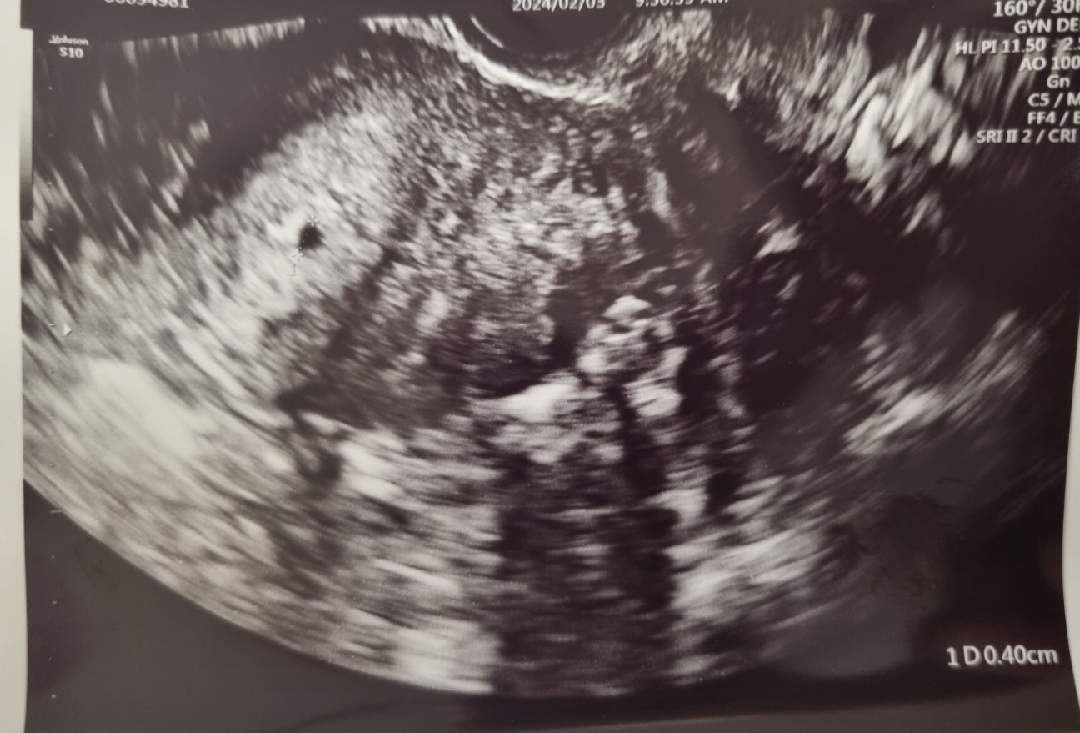

아기집이 너무 한쪽으로 치우쳐져있죠ㅠ?

아기집 보고왔는데.. 저는 왜 이쁘게 가운데 없고 왼쪽으로 치우친걸까여ㅠ?

그냥 촬영한 각도가 그런거 아닐까용??? 병원에 별말 없었으면 문제 없늠걸거에용!!!

저도 왼쪽으로 치우쳐있어용! 병원에서는 별말 없었어요:) 걱정머세요!